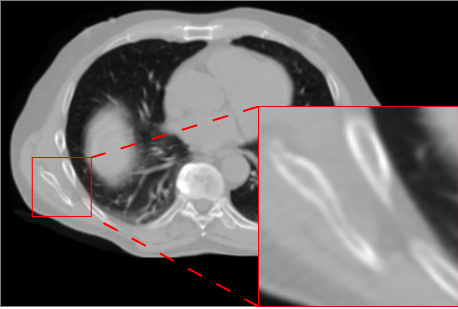

Figure 3 presents qualitative results for the CBCT-to-CT translation task on the HN dataset. The displayed axial slices include a lesion visible inside the brain, allowing a focused assessment of reconstruction quality. Visual inspection shows that AFP-based models generally produce slightly sharper and more accurate reconstructions than L1-only models, with nnResU-Net providing the most precise delineation. In particular, the combination of AFP with nnResU-Net better reconstructs the lesion compared to other configurations.

![]() |

| Input CBCT | nnU-Net L1 | nnU-Net L1 + AFP |

| Real CT | nnResU-Net L1 | nnResU-Net L1 + AFP |